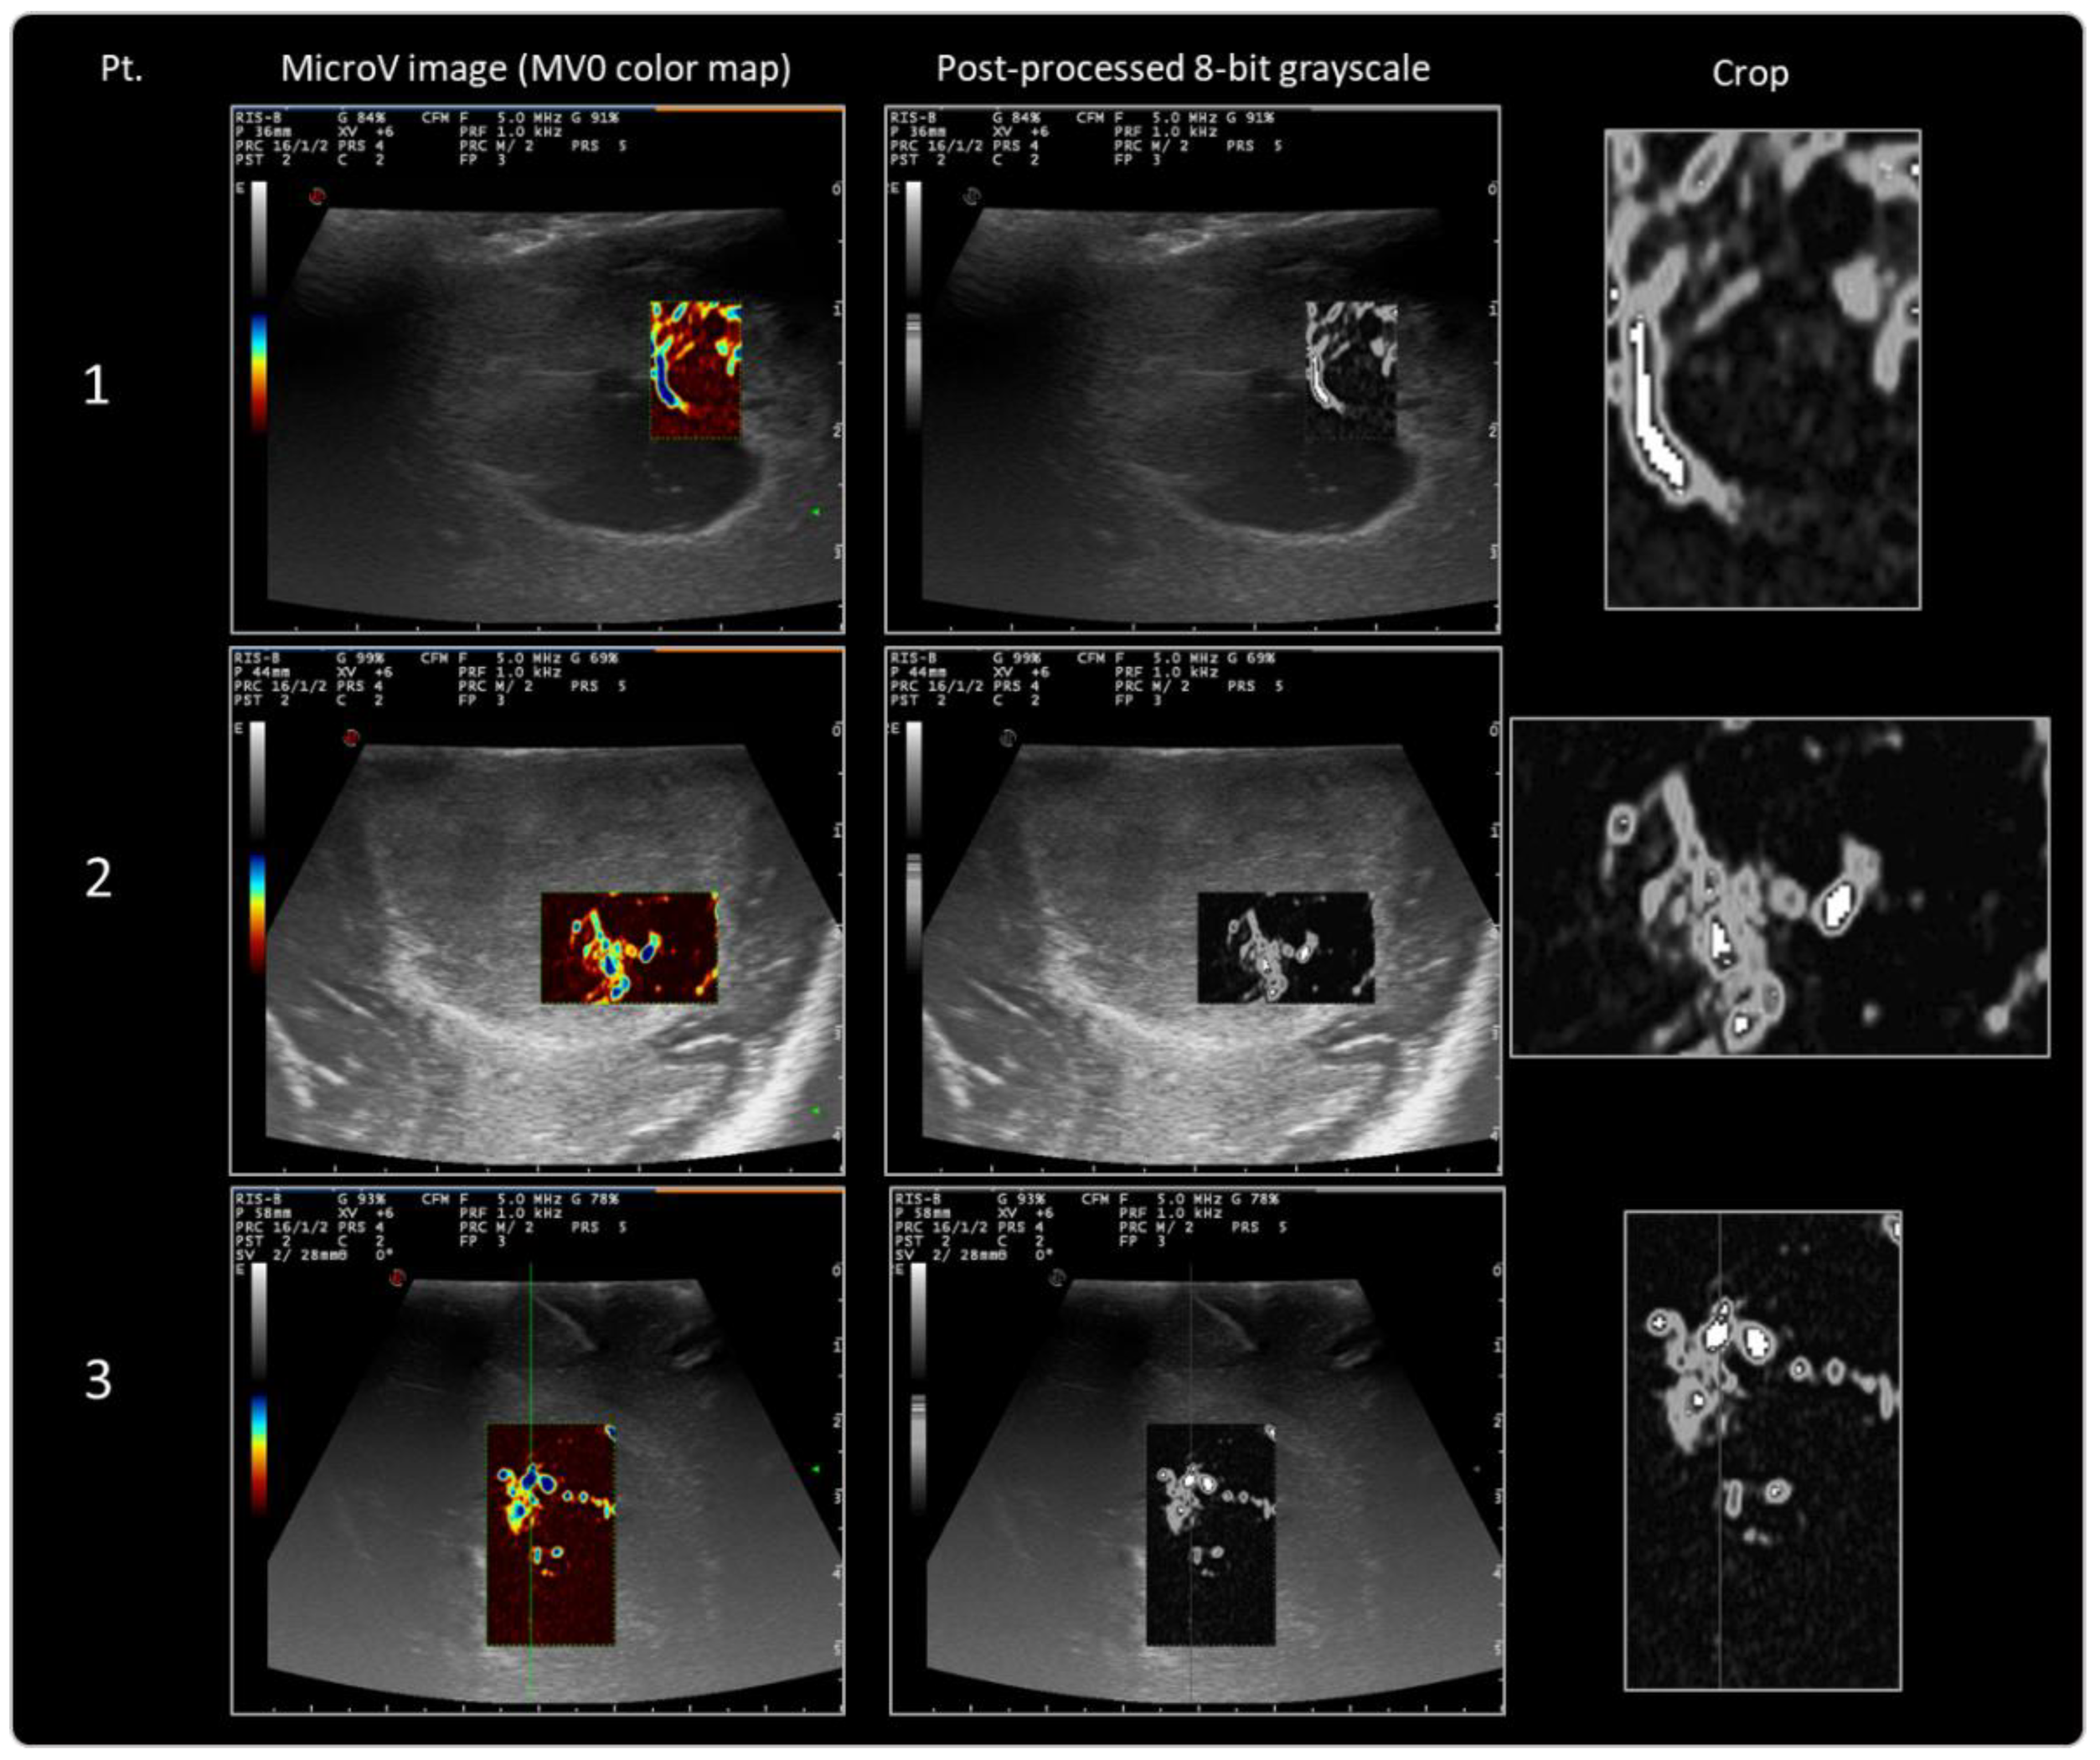

MicroV images which were acquired during IOUS were further post-processed according to the above-defined protocol. Data obtained after post-processing and first-order radiomic analysis are reported in Table 2 and Figure 3, and MicroV images thus processed are ready for further more advanced radiomic analysis (Figure 4). First-order radiomic analysis lies in texture analysis, which quantitatively analyzes how intensity features are spatially distributed inside the MicroV images. Average, minimum, and maximum intensity values, standard deviation, and a histogram with quantitative distribution of pixels within the selected area were calculated on the first eight GBM patients enrolled. Texture analysis represents the first step toward subsequent higher-order analysis, which requires a higher number of enrolled patients and available images.

Figure 4.

Results of MicroV IOUS images with MV0 color map post-processing for internal validation of the protocol.